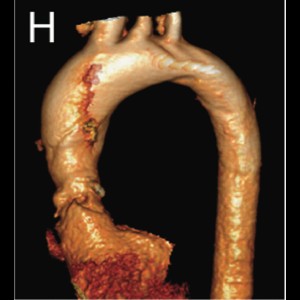

Supra-valvular aortic stenosis in a patient with homozygous familial hypercholesterolaemia

Supra-valvular aortic stenosis in a patient with homozygous familial hypercholesterolaemia

Supra-valvular aortic stenosis in a patient with homozygous familial hypercholesterolaemia

Supra-valvular aortic stenosis in a patient with homozygous familial hypercholesterolaemia

Primary aortic thrombus in young a rare site

Primary aortic thrombus in young: a rare site, a novel treatment

Primary aortic thrombus in young a rare site

Primary aortic thrombus in young: a rare site, a novel treatment